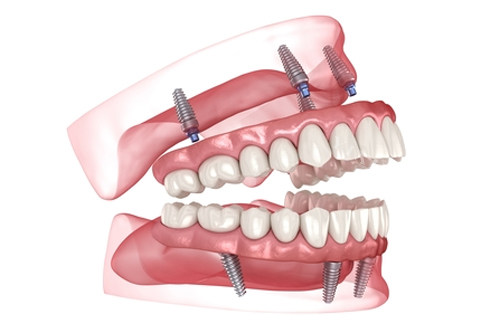

启辰口腔:内江首批引进AI种植牙导航系统的机构,德国3D导板种植技术误差≤0.2mm,支持ALL-on-4全口即刻负重;